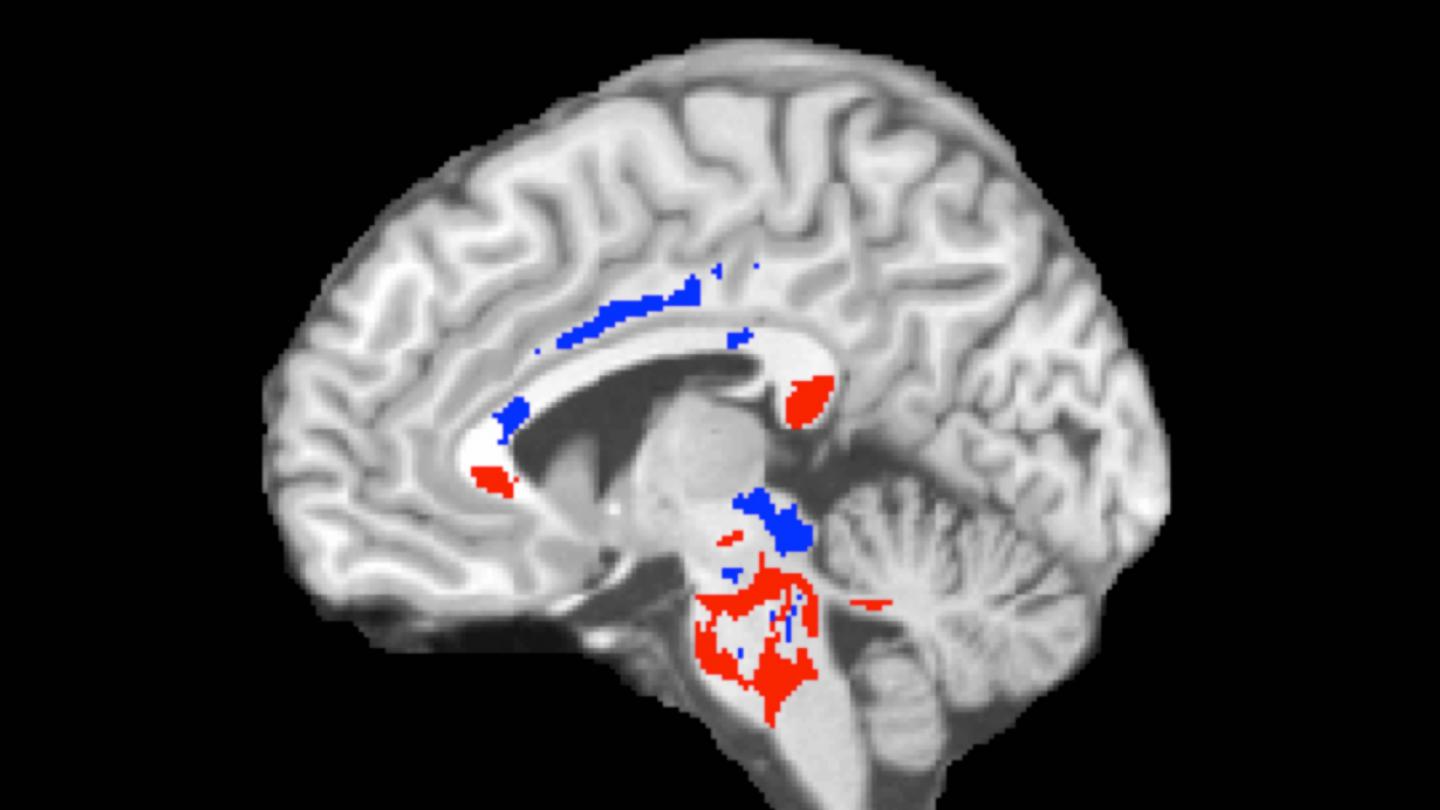

DTI imaging comparing concussion patients and healthy controls revealed two types of white-matter abnormalities in patients: (1) areas of abnormally low FA (red, in associated image) that correlate with axon damage and the cognitive impairment that can affect concussion patients; and (2) other brain areas with abnormally high FA (blue) that may indicate where the brain has responded favorably to injury, perhaps by more efficiently connecting axons or by remyelinating injured tissue (i.e., forming fatty tissue around nerves, which allows nerve impulses to move more quickly).

The amount of high FA imaged in brains predicted patients' outcomes following concussion. Having a greater volume of abnormally high FA white-matter areas (perhaps indicating good compensation for concussion damage) was associated with better outcomes on follow-up assessments. (This doesn't mean that the low FA areas showing white-matter damage aren't important--just that they're not useful in predicting recovery from concussion a year later.)